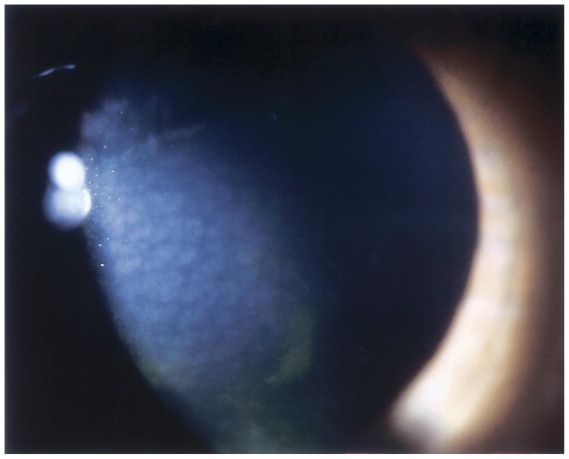

각막에 발생하는 “Crocodile shagreen” (악어가죽 무늬) 같은 불규칙한 반사/혼탁이 특징입니다.

시축의 중심부에 위치하며, 각막의 뒤쪽 기질층에 혼탁이 발생합니다.

세극등현미경 검사 (Slit-lamp)에서 중심 혼탁이 악어가죽 모양의 불규칙한 반사 형태로

우연히 발견되면서, 진단되며,